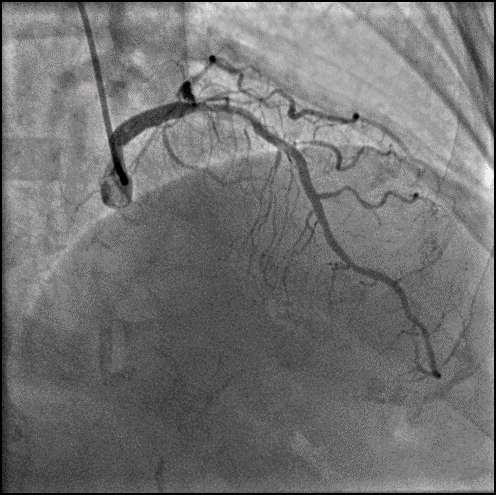

左前降支近段、中段,狭窄程度50-70%,病变长度弥漫性,严重钙化,TIMIⅢ级:第一对角支开口病变,狭窄程度70-90%,病变长度局限性,TIMI Ⅲ级。

回旋支近段,狭窄程度70-90%,病变长度弥漫性,TIMI III级:回旋支远段,狭窄程度90-99%,病变长度弥漫性,TIMI III级;钝缘支,狭窄程度50-70%,病变长度管状性,TIMI III级。

右冠状动脉近段、中段、远段,狭窄程度70-90%,病变长度弥漫性,严重钙化,TIMI III级;

右冠状动脉后降支,狭窄程度70-90%,病变长度管状性,TIMI II级;后侧支,狭窄程度50-70%,病变长度弥漫性,TIMI III级。